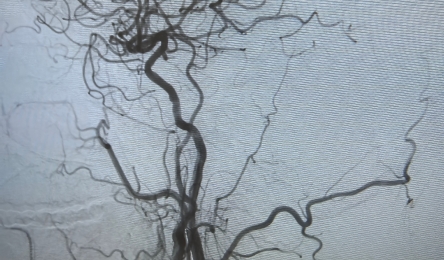

在现代社会,脑血管疾病已成为威胁人类健康的重大隐患。颈动脉狭窄作为其重要诱因之一,时刻潜伏在众多患者的身边,而颈动脉支架植入术的出现,如同一束希望之光,为患者带来了新生。